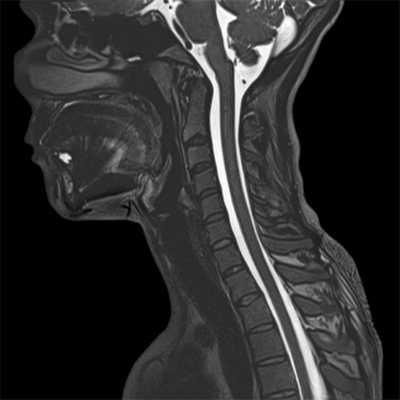

Фото томографии шейного отдела

Сделанные в ходе КТ фото - это срезы шейного отдела позвоночника в нескольких проекциях. Рассматриваемая зона сканируется под разными углами, и пациенту не нужно менять свое положение. Так как съемка захватывает не только собственно шею, но и прилегающие участки, специалист получает достаточно информации, чтобы в полной мере оценить любые патологические изменения.

Главное достоинство КТ шейного отдела позвоночника - высокая точность фото и возможность преобразовать множество плоских картинок в объемную модель, которая покажет все анатомические особенности заданной области. Программное обеспечение томографа позволяет увеличивать снимки для более детального рассмотрения, качество от этого не меняется.

Деформирующий спондилез (образование костных наростов) в шейном отделе позвоночника